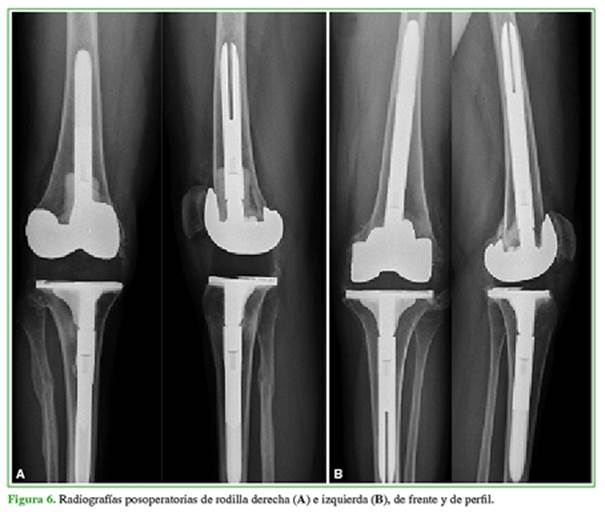

Se realizó un RTR bilateral en un solo acto quirúrgico (Figura 5). Se utilizó una prótesis estabilizada posterior con vástagos tibial y femoral para ambas rodillas. No tuvo complicaciones en el posoperatorio inmediato ni tardío. A los cuatro años de la cirugía, el rango de movilidad es de 100° y la extensión de ambas rodillas es completa. El KSS mejoró notoriamente a 87/90 en la derecha y 80/90 en la izquierda. En las radiografías, no se observan signos de aflojamiento de la prótesis (Figura 6). Refiere estar satisfecho con el procedimiento.